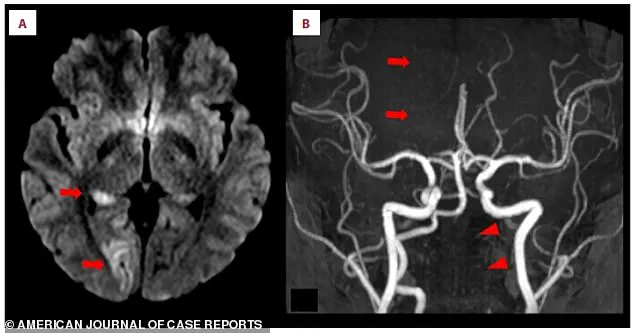

Doctors, upon examining her brain scans, discovered acute ischemic stroke in the right occipital lobe, a region critical for visual processing.

The MRI images, marked with arrows, revealed bright white spots—evidence of brain tissue deprived of oxygen due to blocked blood flow.

The scans also exposed a more ominous detail: a missing section of the right posterior cerebral artery, the key blood vessel supplying the brain.

This artery, normally a smooth, continuous line, had a distinct gap, indicating a blockage.

Further investigation revealed a crescent-shaped blood clot embedded within the left vertebral artery, a vital conduit for blood to reach the brain.

This artery, visible in the scans, appeared faint and thin, signaling restricted blood flow.